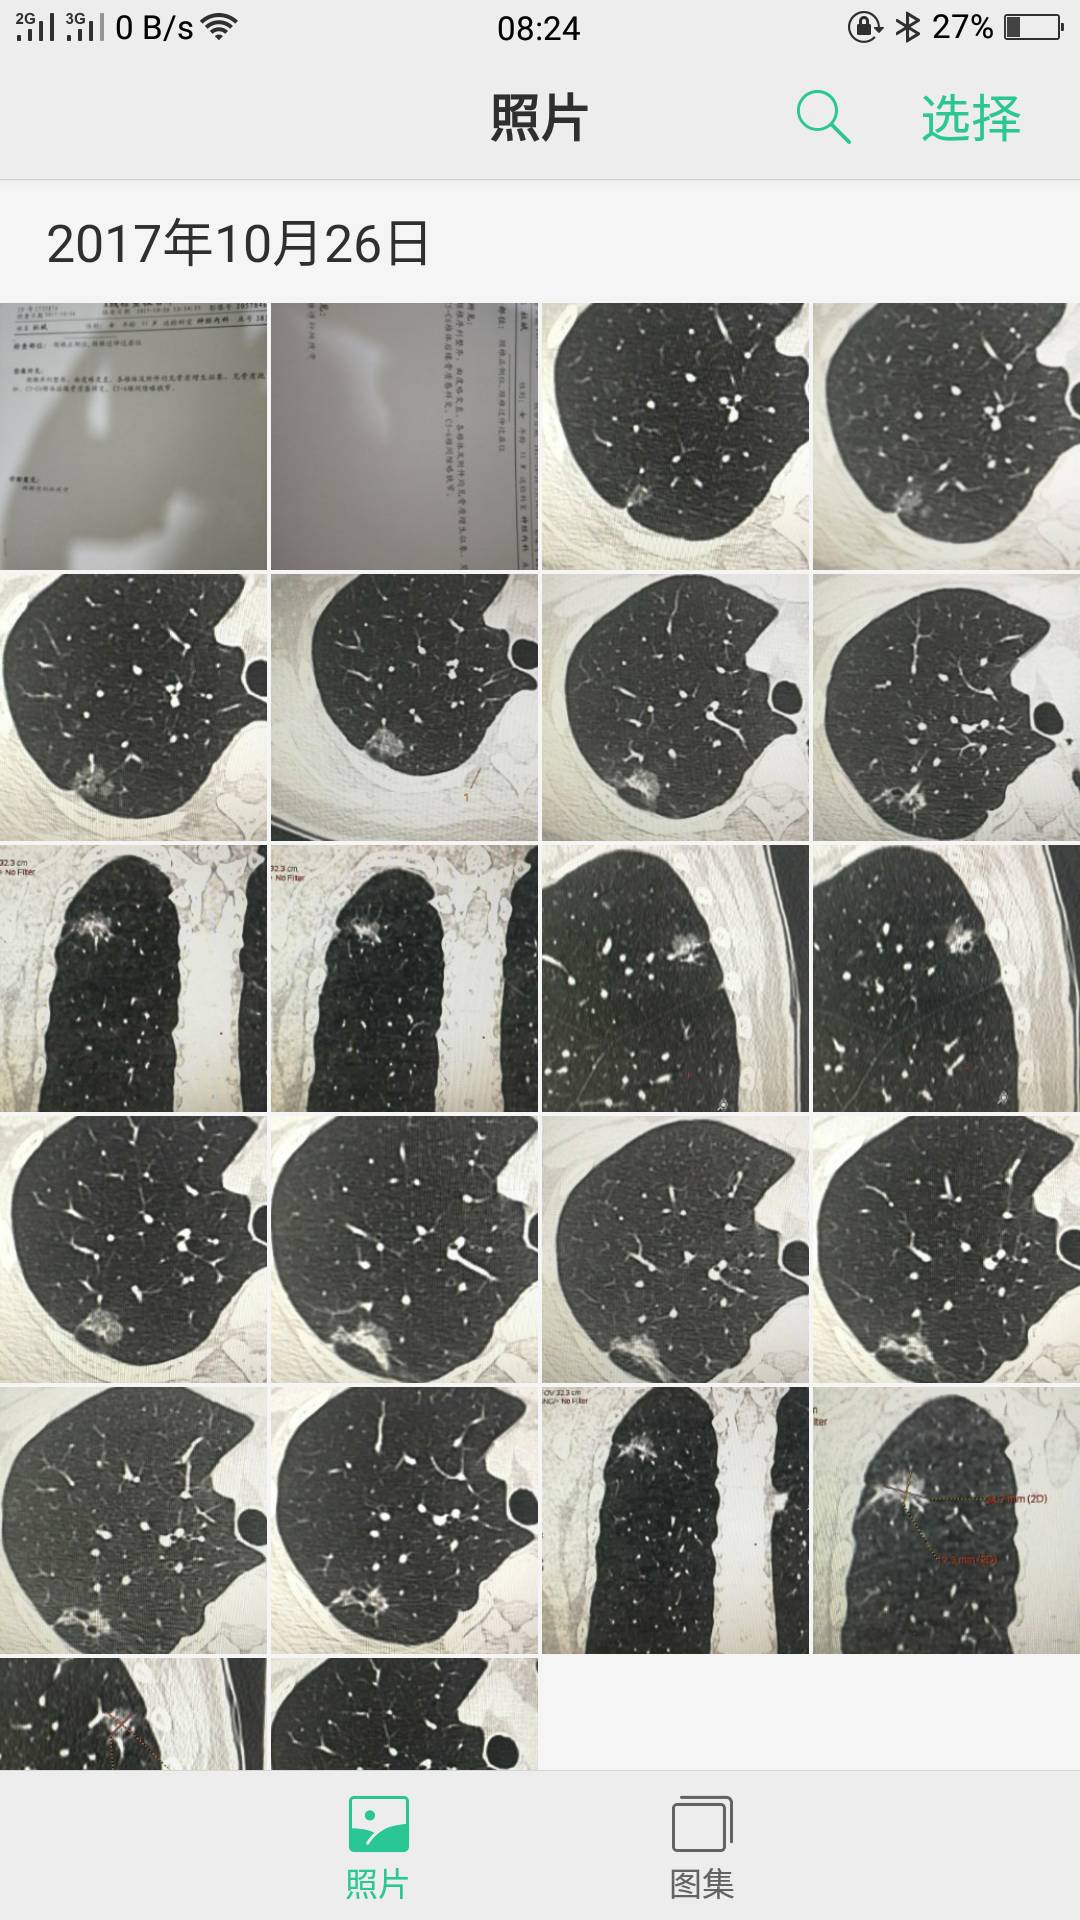

您好,陈大夫,我的图片都是别人从电脑里发给我的,我一点也看不懂哪个是左肺的哪个是右肺的,这就是所有的图了,我这样发给你不知道行不行?谢谢您了,认真负责的好大夫啊!现在这样的大夫少见啊!

这张

这张

陈波医生把左右两边的一起拍一个镜头里,应该还是局限在右上肺的原位癌,但还是想看全肺把其他地方排除一下

陈波医生有时间把CT报告发我看看,你是哪个省的,你这个要找手术做得好的,肺癌治疗这个概念太广了